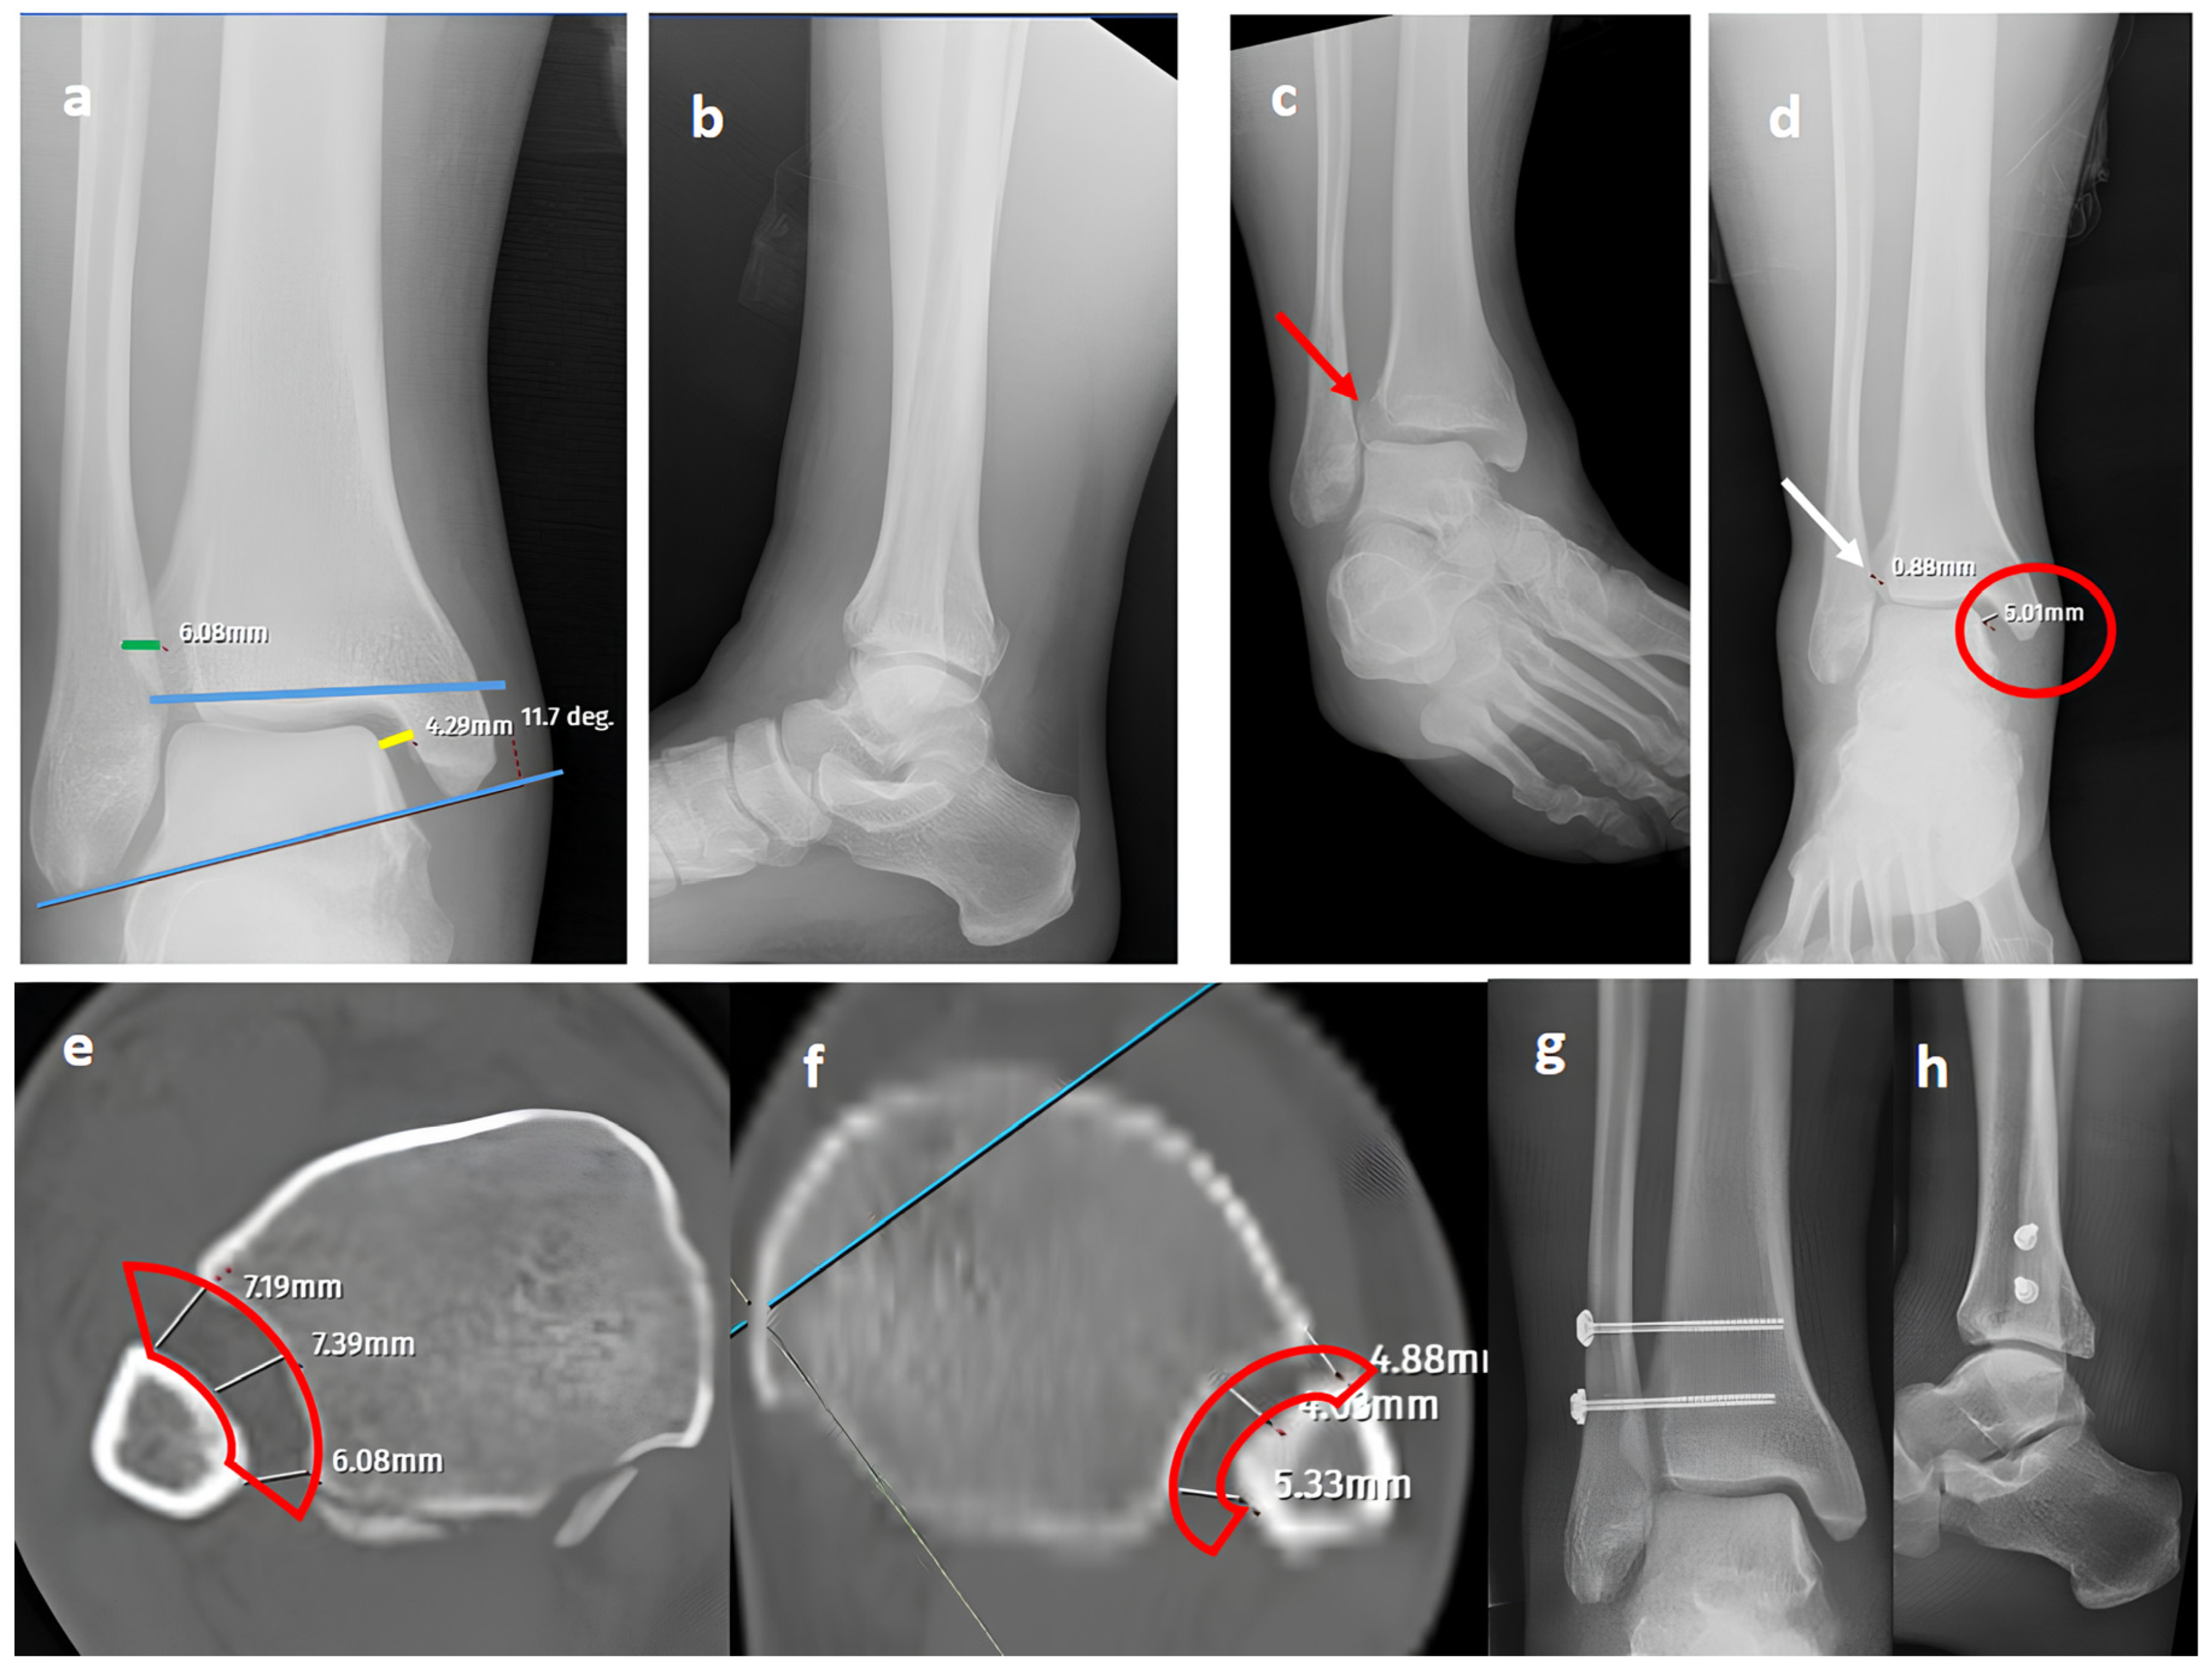

Figure 2.

A Maisonneuve (pronation-external rotation IV) fracture. (a,b) Standard AP and lateral views showing a posterior malleolar fracture with a normal distal tibiofibular (green line) overlap, medial clear space (yellow line), and talocrural angle (blue lines). (c) A mortise view showing an obviously widened distal tibiofibular distance (red arrow), indicating syndesmosis injury. (d) A GAASA view showing lateral displacement of the talus with widening of the medial clear space (red circle) within physiological limits, indicating that the deltoid ligament is intact. However, widening is still evident for the distal tibiofibular distance due to syndesmosis injury (white arrow). (e) A comparison of axial CT images of the injured right ankle and axial CT images of the uninjured left ankle (f) reveals obvious distortion of the whole syndesmosis (red block bows) for the right side. (g,h) Postoperative X-rays showing reduction and fixation of the mortise without the need for the intervention of posterior structures, indicating that the deltoid ligament is intact, consistent with the GAASA image.

In our series, 19 of 36 SER type II and IV cases did not involve syndesmotic injury (Figure 1), which is consistent with the idea that medial and lateral injuries must be carefully assessed before surgical stabilization. These findings highlight that GAASA imaging is particularly reliable in PER injuries, where all medial and lateral structures are disrupted and the fibula is extensively fractured. In such cases, gravitational force causes the talus to exert downward pressure on the distal fibular fragment, producing clear widening of the medial clear space and distal tibiofibular joint [28]. Maisonneuve injuries, not classified by the Lauge-Hansen system, are inherently unstable and require surgical syndesmosis stabilization [29]. In our study, three cases had clear distal tibiofibular widening without pathological medial clear space widening (Figure 2). This contrasts with the cadaveric study by Krahnebühl et al., which reported that stress radiographs are reliable only when deltoid and syndesmotic injuries coexist, but are ineffective for isolated syndesmosis injuries [5]. Our findings suggest that even when the medial malleolus and deltoid ligament remain intact, gravitational force alone can cause lateral fibular displacement, resulting in decreased tibiofibular overlap.